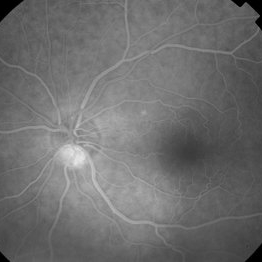

Central Serous Chorioretinopathy

Central Serous Chorioretinopathy

Jan 25 2022 by Olivia Rainey

Late phase widefield fluorescein angiography of a 60-year-old male with Central Serous Chorioretinopathy. Chronic history of CSR followed with observation without treatment prior to presenting at our office. The physician noted significant findings on exam and imaging with multifocal areas of inactive and active changes OD. FA shows superotemporal macular leakage, subtle inferonasal macular leakage and staining as well as multifocal hypercyanescence on ICG. Fortunately foveal sparing and thus observation is recommended at this time OD.

Photographer: Olivia Rainey, OCT-C, COA

Imaging device: Heidelberg Spectralis

Condition/keywords: 55-degrees, central serous chorioretinopathy (CSCR), central serous retinopathy (CSR), chronic central serous chorioretinopathy (CSCR), fluorescein angiogram (FA), fluorescein leakage, heidelberg spectralis, indocyanine green (ICG) angiography, late phase